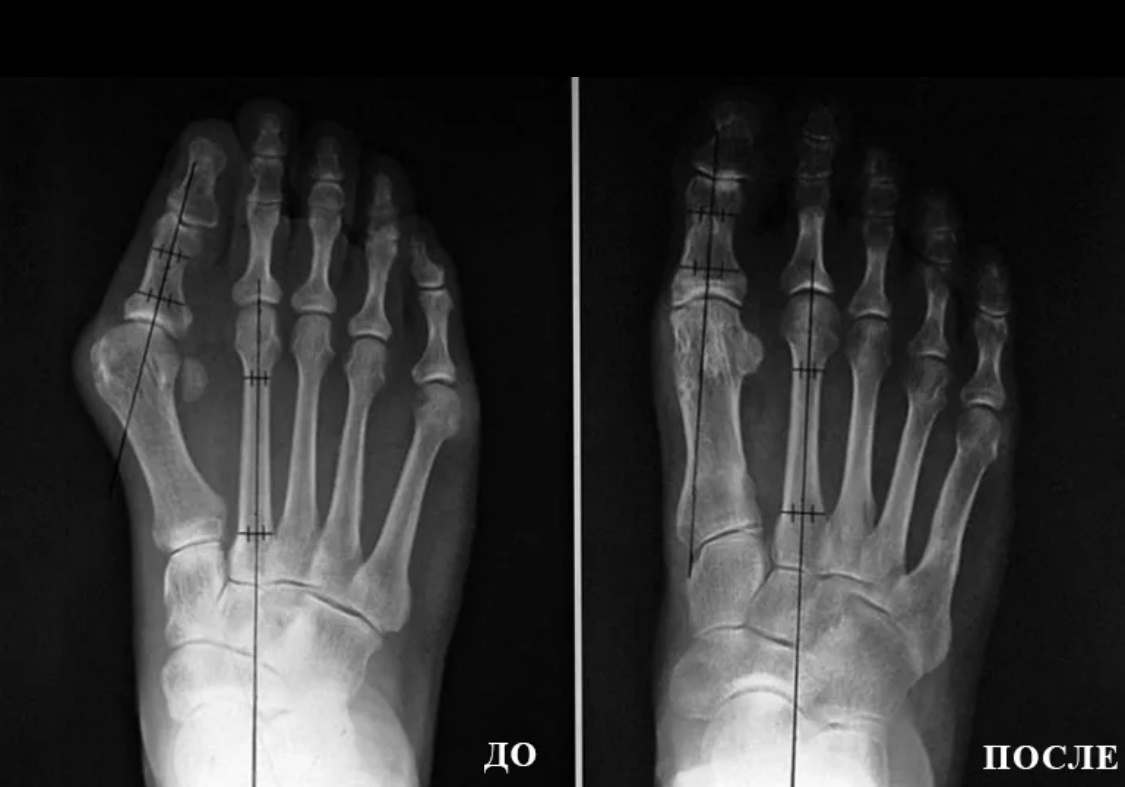

Вот здесь - классика. Перепилили две кости - зафиксировали две кости.